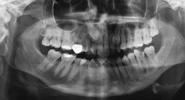

Dr.Handan Tuğçe Oğuz kliniğinde her yaş grubu hasta için gerekli tüm ortodontik tedavileri gerçekleştirmektedir. Ortodontik tedavilere ek olarak Horlama ve Obstrüktif uyku apnesi hastalarının ağız içi aygıtlarla tedavilerini de yapmaktadır.